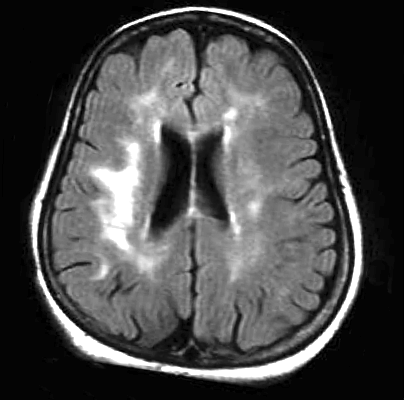

Il progredire della leucoaraiosi tende a seguire un modello generale. Inizialmente si osservano le lesioni periventricolari verso i bordi dei ventricoli laterali (Fig.1), estendendosi queste, in seguito e secondo la gravità del fenomeno, intorno ad essi (Fig.2).